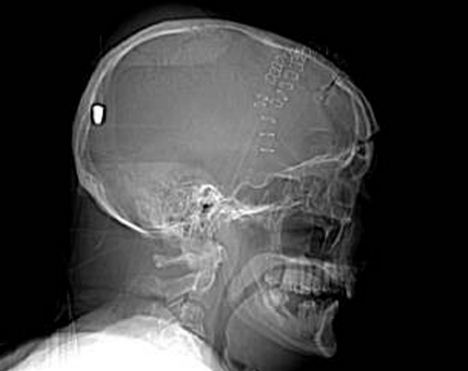

CT扫描显示子弹留在彼得老人的脑部

据英国《每日邮报》5月11日报道,英国一名61岁的老人上个月19日在花园干活时被一颗流弹击中脑部竟奇迹存活,目前他半身瘫痪但无生命危险。5月10日,警方为了破案公布了彼得先生的脑部扫描图片,希望知情者提供相关线索。

事情的经过是这样的,彼得在整理花园的时候突然摔倒在地不省人事,他的家人还以为他中风了,但医院对其大脑扫描后却发现了令人惊悚的事实:一颗子弹不知由于何种原因从左眼窝进入他的大脑,并深深植入其脑后部。但不可思议的是彼得竟然活了下来,虽然身体部分瘫痪且失去了语言和记忆能力。

医生说开颅取弹手术风险巨大,很可能危及彼得生命,所以只能放弃这个计划。彼得先生已经被告知事故经过,但他自己什么也想不起来了,医生认为他患了健忘症。除了损伤左眼视力外,彼得先生身体右下半部分也已瘫痪。他的发音都很含糊,记忆也是支离破碎的,目前大部分时间都在睡觉,但病情还算稳定。

负责调查此案的警官史蒂夫表示:“这可能是我调查过的最诡异的一个案子了。”经过对扫描图片的鉴定,警方弹道专家贾尔斯认为这颗子弹很像是从一种通常用于射杀兔子的.22口径猎枪里射出的。

“如果在10码外开这种枪,子弹会穿透彼得的脑部,但若是从800到1000码以外,子弹会失去大部分的冲击力,只能穿透软组织。所以说,在这个距离内,子弹若射中彼得脑壳会被弹回,不可能进入脑中,”贾尔斯说。